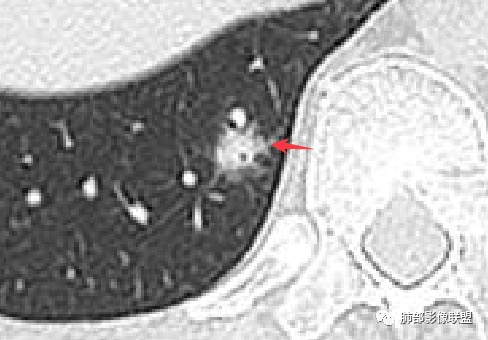

继续看。病变的偏远端依然有支气管通行。

病变的定位,是次级肺小叶内,包绕小叶中心结构,并且有一部分病变是局限于一个腺泡结构的,也就是Reid'S小叶;

我们先分析支气管。刚才的截图是明确可以看到支气管显示的。那么它是扩张吗?

再来。注意看病灶下缘的这个支气管,这里几乎没有病灶了。与周围临近的支气管相比。

所以,这些支气管显影,大概率不是牵拉支扩,而是肺泡填充以后的支气管显影。当然,可能存在轻微的支气管扩张。但是,已经不是病变的主要因素。后面还有证据支持。